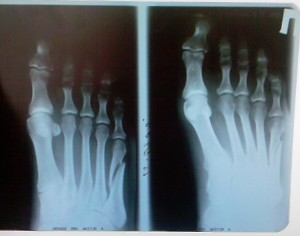

Основание для диагноза при подобном переломе

Диагноз выставляется на основании:

- анамнеза травмы, осмотра пораженной конечности (деформация сводов, диспозиция мизинца, наличие выпирающего костного отломка и т.д.)

- рентгенографии свода стопы.

Диагностику лучше всего проводить непосредственно после получения травмы, так как со временем возможно ложное дифференцирование перелома с массивным процессом резорбции кости, из-за чего пациент получит лечение не в полном объеме.